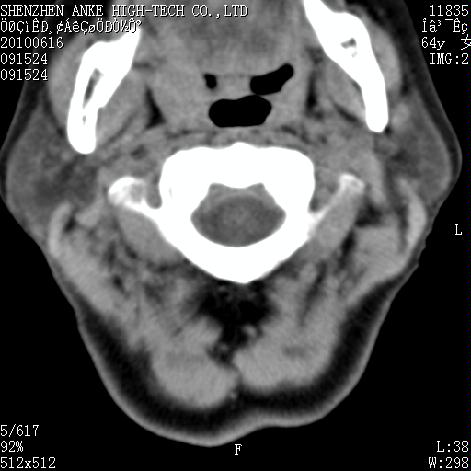

标题: CT27132:患者女,64岁,颈部及全身多处包块,现觉吞咽困难4 [打印本页]

标题: CT27132:患者女,64岁,颈部及全身多处包块,现觉吞咽困难4

右侧甲状腺占位,肿瘤可能性大,癌

右侧甲状腺癌伴右颌下腺淋巴结转移

右侧甲状腺癌伴淋巴结转移

右侧甲状腺癌伴淋巴结转移可能性大

右侧甲状腺癌伴淋巴结转移可能性大。

右侧甲状腺癌伴右颌下腺淋巴结转移!建议增强!